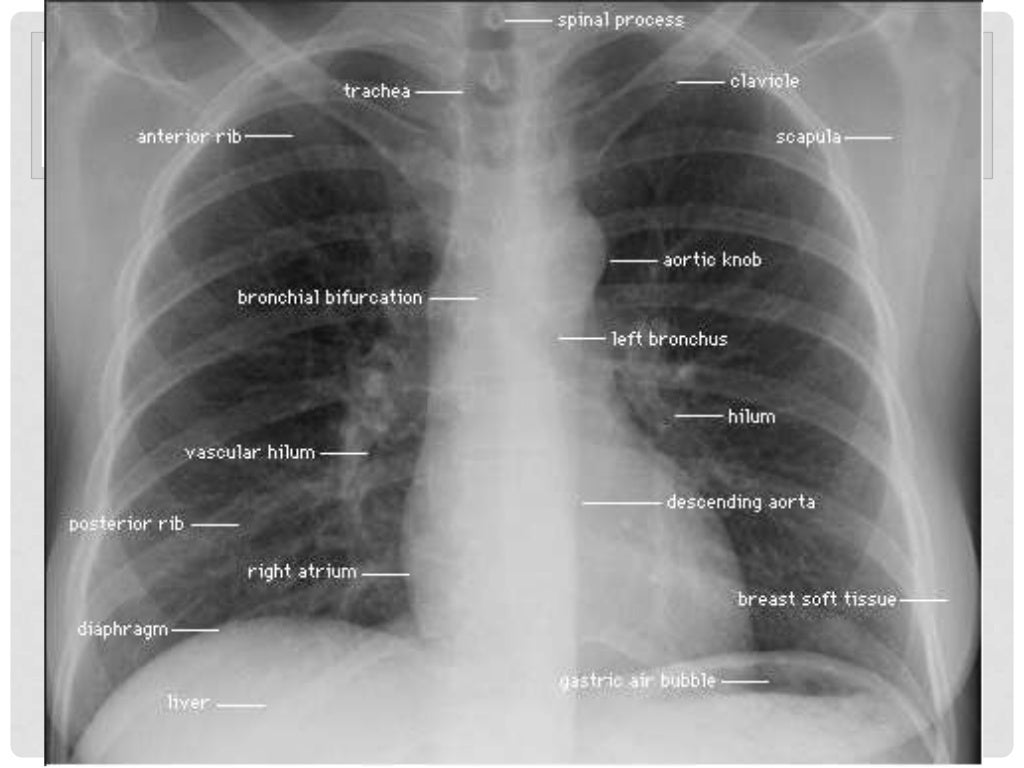

Side of X-ray (look for right “R” and left `V markers on the top of the film).Position of the patient (look for kyphoscoliosis).Always remember to assess the technical quality of the film, such as incorrect exposure or faulty centering or projection, which may either hide, mimic or confuse with the disease diagnosis. In a CXR, carefully observe the following points. However, a pneumothorax is more clearly seen in an expiratory film rather than in the inspiratory film.